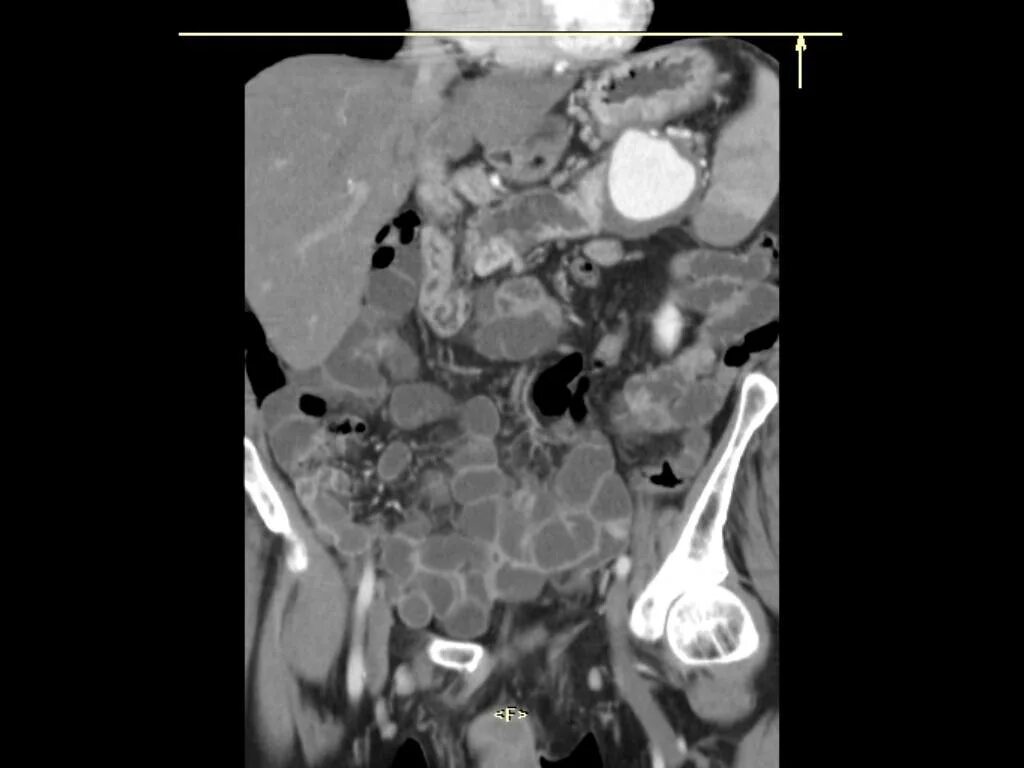

Воспаление брюшных лимфоузлов причины